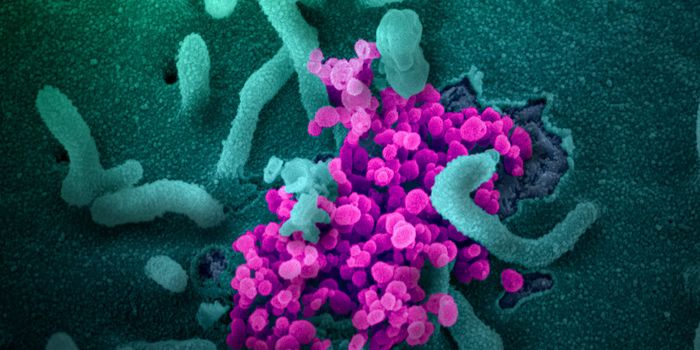

JUL 05, 2020Cell & Molecular BiologyThe pandemic virus SARS-CoV-2 enters the body through the respiratory system to cause the illness COVID-19. But we know ...